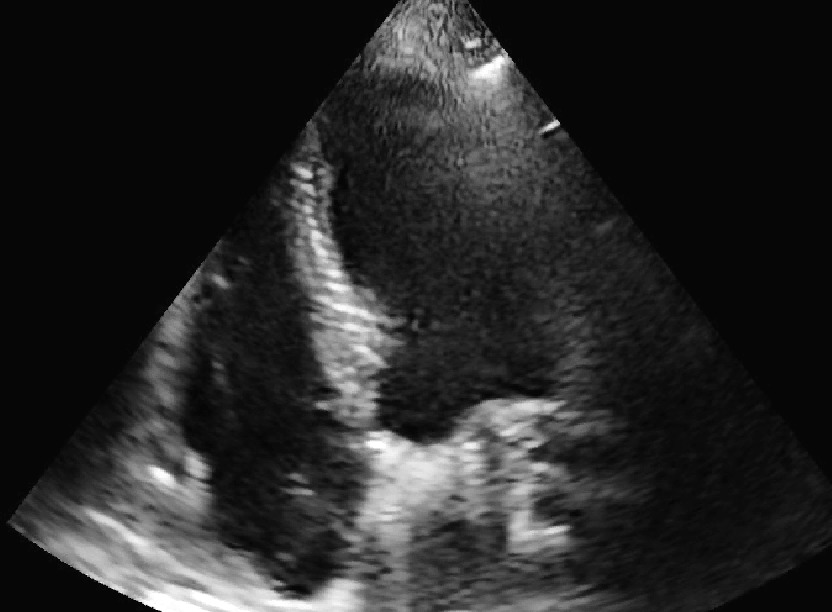

Infarto ventricolare dx

Laura Massironi